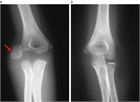

1. X線、CT、MRIなどの画像診断やエコーは病変の局在、程度を知るために重要である。